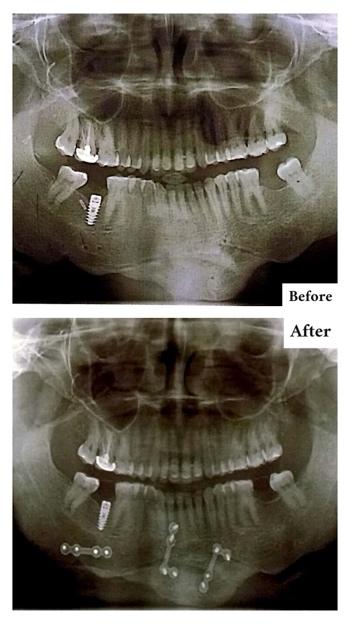

Case Study | Tumour and Cyst